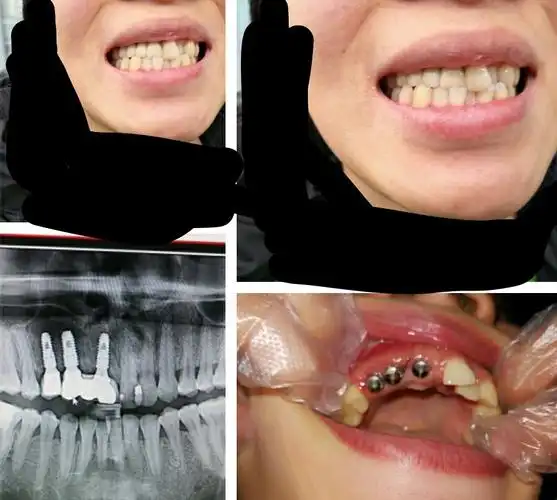

种植牙修复一例 - 好大夫在线